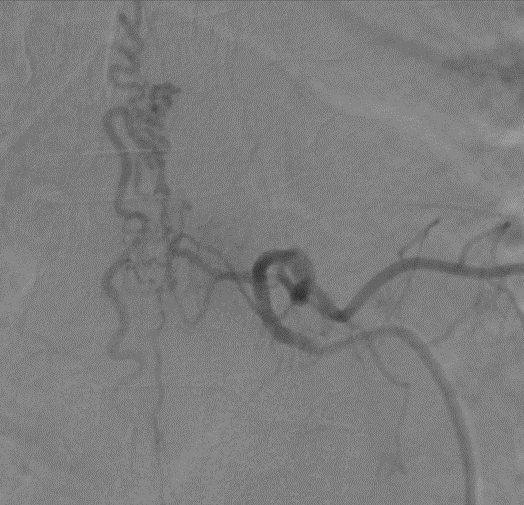

Trái tim là cơ quan quan trọng nhất trong cơ thể, đảm nhận vai trò bơm máu giàu oxy và dinh dưỡng đến nuôi các cơ quan, tế bào trong cơ thể. Bản thân trái tim cũng có 1 hệ thống mạch máu nuôi các tế bào cơ tim được gọi là hệ mạch vành. […]